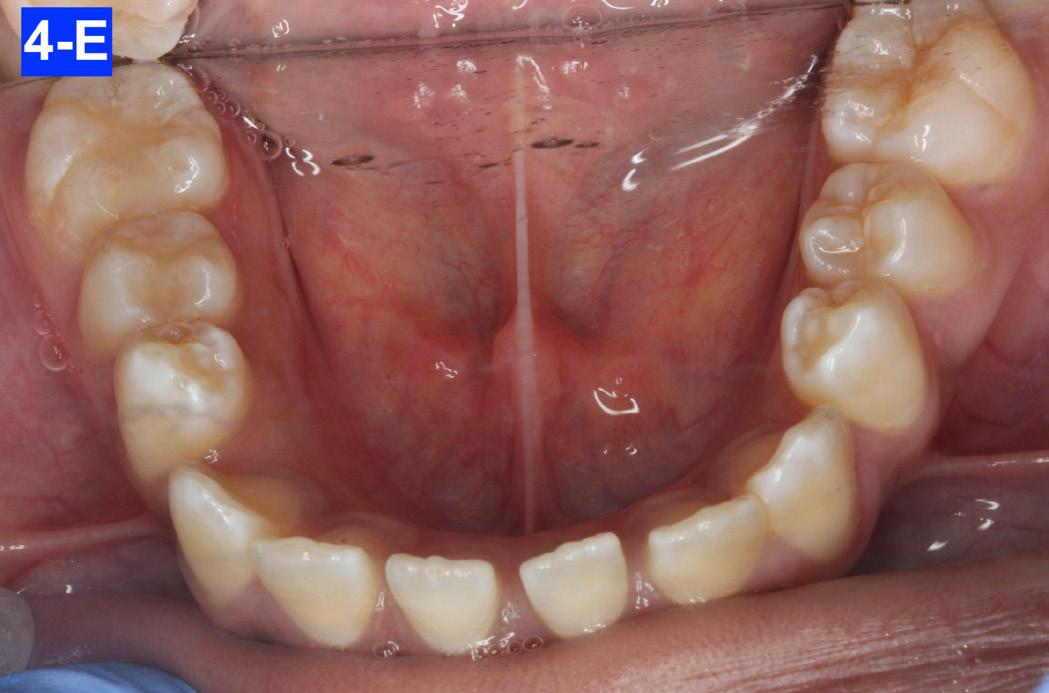

Clinical Micro-esthetic appraisal revealed a full Angle Class I molar and cuspid relationship. The arches were wide, there was generalized spacing in the anterior region. The patient had 2.0 mm overjet and -3.0 mm overbite. Maxillary lateral incisors appeared to be microdonts (Figures 4-A, B, C, D).

Fig. 4-E: Pre-treatment, MN occlusal view

Fig. 4-D: Pre-treatment, MX occlusal view